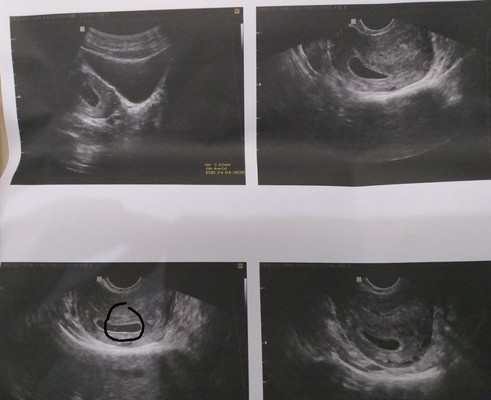

Bunda maaf ingin sharing, hamilku 7 week baru ada kantung dan di dlm kantung baru ada yorkshak (kuning telur) atau makanan si janin. Masalahnya yg makan siapa? Janinku katanya belum ada. Adakah yg 1 pengalaman dgnku bun? Ada yg blg kuning telur itu bakal jadi janin bun. Itu yg saya lingkarin bun kuning telurnya. Klo emg gak ada janinnya aku BO soalnya kata dokternya aku gak mual gitu bun. Gimana ya bun???

Baca lagiBun sy jg usia 8 weeks baru cadangan makananny aja, janin ny belom. Percaya aja, manusia sdh d ksh rejeki bahkan sblm kita ny diciptakan, buktinya kita udh d ksh makanan sblm kitanya ada. Terus saya ush lg, 12 week udh ada janinnya kok malah sehat bgt dy. Itu jg keliatanny klo usg transvaginal aja. Tetap positif thinking, setiap kehamilan itu beda2. Berdoa selalu yg terbaik y bund, sy doakan jg Nnti cek 2 minggu-sebulan lg. Ganti dokter. Skrg sy usia kandungan 27 weeks alhamdulillah sehat2 bun.